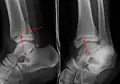

A triplane fracture of the ankle as seen on plain X-ray

- Triplane fractures are a special type of fracture that involves the immature skeleton. It has a coronal plane in the metaphysis, an axial plane in the physis, and a sagittal plane in the epiphysis.[14]